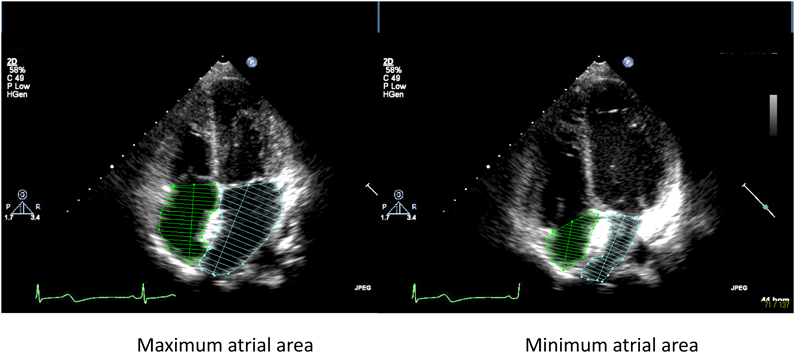

解析画像は,小児心臓超音波検査トレーニングを受けた循環器小児科医および超音波検査士により記録した画像中,両心房が十分に描出された心尖部四腔断面の動画像を用いた(Fig. 1).

Fig. 1 Tow-dimensional echocardiograms from apical four-chamber

心尖部四腔断面から計測した房室弁開放直前の最大心房面積(Max),房室弁閉鎖直後の最小心房面積(Min)を求め,心房reservoir機能の指標として,心房伸展性Distensibility(Dis)[=(Max−Min)/Min]を計算した4–6)